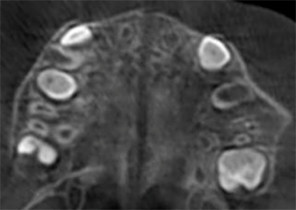

10 ans et 0 mois, 18 étapes d’appareils d’expansion palatine Invisalign

Avec l’aimable autorisation de la Dre Sandra Khong Tai

Avant le traitement d’expansion avec les appareils d’expansion palatine Invisalign

Après le traitement d’expansion avec les appareils d’expansion palatine Invisalign

Après le traitement Invisalign First

Avant le traitement d’expansion avec les appareils d’expansion palatine Invisalign

Après le traitement d’expansion avec les appareils d’expansion palatine Invisalign

Après le traitement Invisalign First

Étude de cas 2

7 ans et 11 mois, 24 étapes d’appareils® d’expansion palatine Invisalign.

Avec l’aimable autorisation du Dr David R. Boschken

Avant le traitement d’expansion avec les appareils d’expansion palatine Invisalign

Après le traitement d’expansion avec les appareils d’expansion palatine Invisalign

Après le traitement d’expansion avec les appareils d’expansion palatine Invisalign

Avant le traitement d’expansion avec les appareils d’expansion palatine Invisalign

Après le traitement d’expansion avec les appareils d’expansion palatine Invisalign

Après le traitement d’expansion avec les appareils d’expansion palatine Invisalign